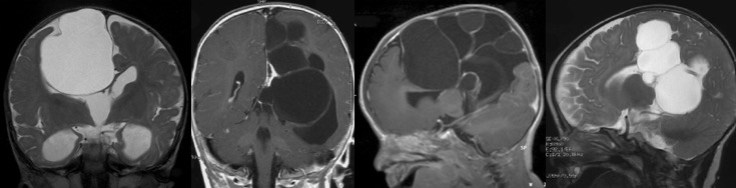

on regroupe sous ce terme des kystes dont la paroi n’est pas méningée mais constituée de tissus cérébraux. il s’agit d’un ensemble très divers de pathologies rares, qui peuvent être diagnostiquées en anténatal.